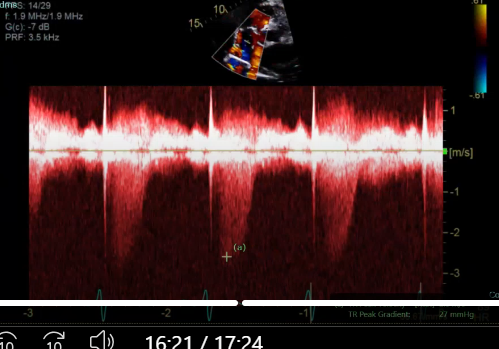

what measurement is this for

TR, peak the TR

IVRT, perform CW between aortic valve and AMVL for IVRT (measure AVC-MVO)